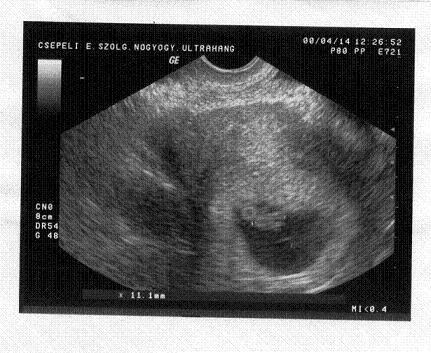

Én november legvégére várom és most így néz ki.

Kép

Csepelen lakom.